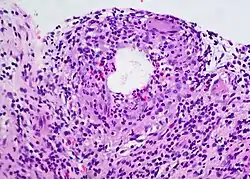

A chalazion (/kəˈleɪziən/; plural chalazia or chalazions) or meibomian cyst[4] is not a cyst but a granuloma[5] in the eyelid that results from a blocked meibomian gland.[6][7] It typically occurs in the middle of the eyelid, red, and not painful.[2] They tend to develop gradually over a few weeks.[2]

A chalazion may occur following a stye or from hardened oils blocking the gland.[2] The blocked gland is usually the meibomian gland, but can also be the gland of Zeis.[8]